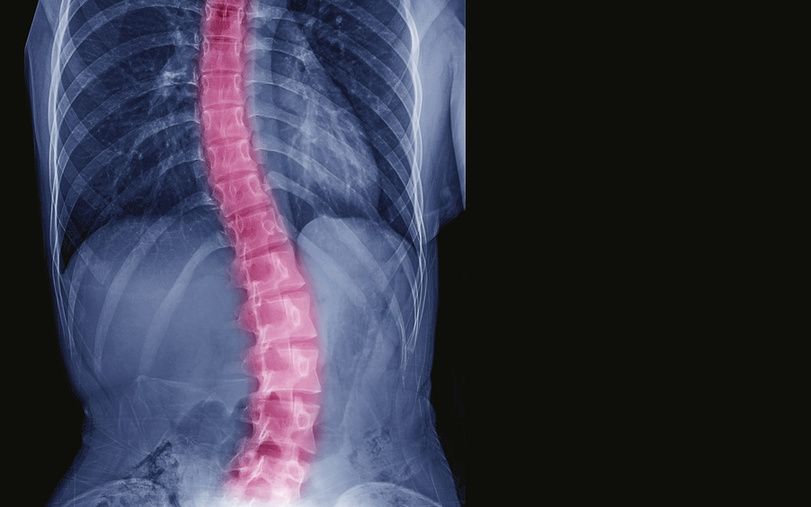

“脊柱位于背部正中,上端接颅骨,下端达尾骨尖,是人体的中轴骨骼,有负重、减震等功能。”朱如森介绍,“脊柱侧弯是一种脊柱的三维畸形,包括冠状位、矢状位和轴位上的序列异常。通俗来说,就是脊柱偏离正常中线产生的畸形,同时还伴随着脊柱的旋转,就像拧麻花一样。”

“脊柱分颈、胸、腰、骶及尾五段,正常的脊柱呈S形。”朱如森介绍,脊柱每一部分的作用以及承受的力并不一样,脊柱上部较长、灵活性强,好似支架,悬挂着胸壁和腹壁;脊柱下部较短、灵活性差,身体的重量和所承受的震荡即由此传达至下肢。